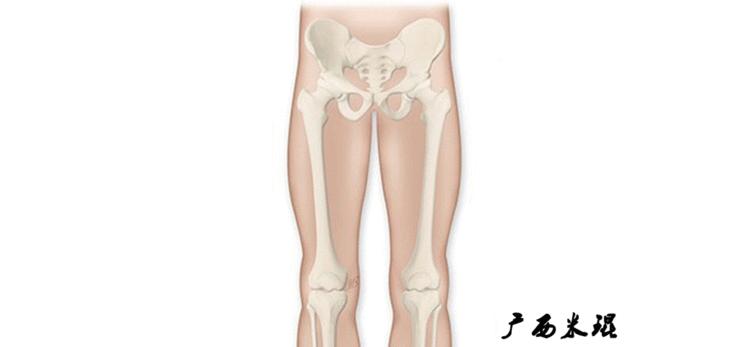

1、判定有无畸形

下肢的畸形定义为生理轴线的偏移。关节角和轴线在冠状面、矢状面和横断面上可发生病理改变,并引起整个下肢的对线异常。

最常见的下肢畸形发生于冠状面,即膝内外翻畸形,冠状面的对线异常通过应用“对线异常检验”进行分析,机械轴的偏移(MAD)表现为对线异常。

膝内翻是指下肢力线通过膝关节中心点内侧,距中点2mm以上,偏内超过15mm为显著膝内翻。膝外翻是指下肢力线通过膝关节中心点外侧,距中点2mm以上,偏外超过10mm为显著膝外翻。